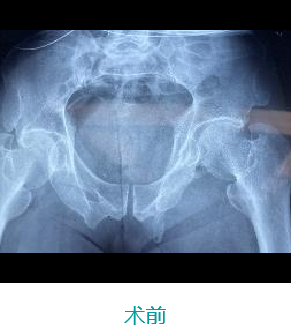

天玑II 辅助骶髂螺钉(S1-S2)、前柱顺行经皮空心螺钉内牢靠术

基本情形:患者男,,,,,,61岁,,,,,,骨盆骨折

病例泉源:北京积水潭医院